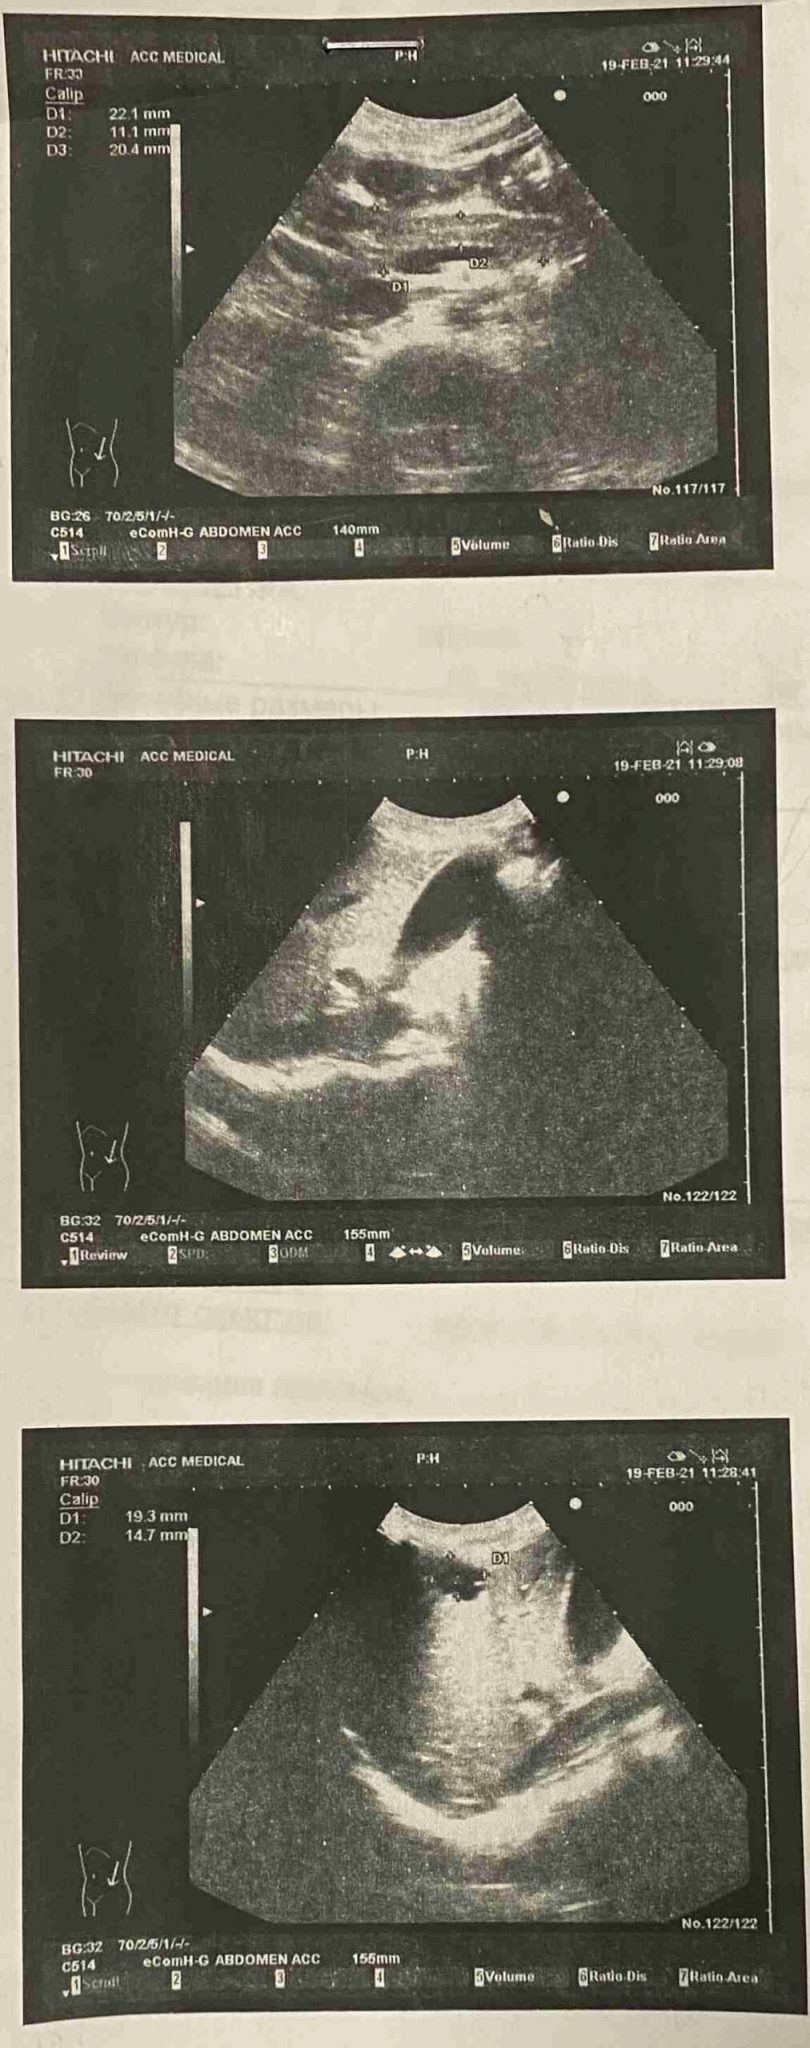

Лапароскопічне видалення вузла глибокого інфільтративного ендометріозу, уретеролізіс лівого сечоводу, видалення двобічних єндометріом.